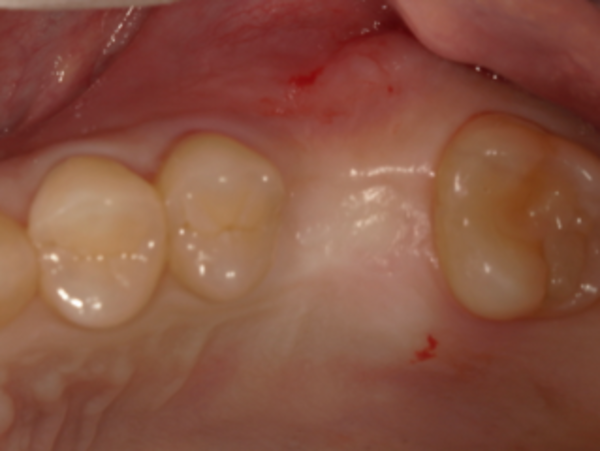

② 診断

抜歯4ヶ月後に、治療部分のCTの撮影を行い、骨の形、量、幅などインプラント治療が可能かどうかを評価しました。

抜歯部には十分な骨の量があり、インプラント治療が可能であると判断しました。